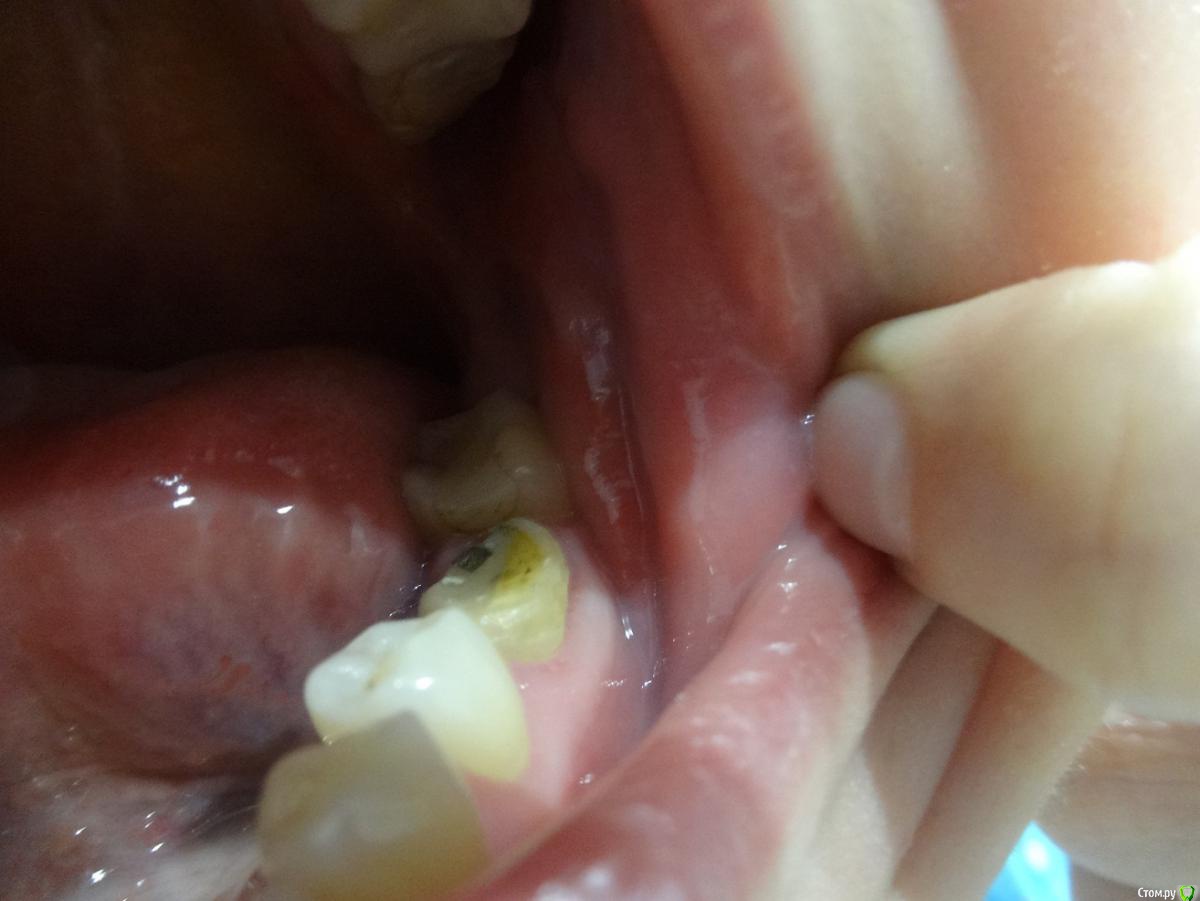

lepestochek Опубликовано 5 ноября, 2015 Поделиться Опубликовано 5 ноября, 2015 (изменено) Здравствуйте! Хотелось бы услышать профессиональную оценку по поводу жевательного зуба 36. Более 10 лет на нём стояла коронка. На снимке врач увидел воспаление у корня и предложил протезирование коронкой из диоксида циркония и, вероятно, вкладка( точно скажет на следующем приёме), предварительно пролечив каналы. После чего воспаление должно со временем исчезнуть. Коронку сняли( фото). На внутренней стороне нет стенки, поэтому хотелось бы знать надёжно ли будет предложенное лечение. А если и возможно, то нельзя ли металлокерамической коронкой накрыть? 15 зуб подготовили под культевую вкладку из кобальт хрома и коронки из диоксида циркония, так как металлокерамика сказали не будет держаться. И это немалые деньги. Ещё раз прошу, подскажите, стоит ли 36 зуб таких затрат? Спасибо. Изменено 5 ноября, 2015 пользователем lepestochek Ссылка на комментарий

4ebstom Опубликовано 6 ноября, 2015 Поделиться Опубликовано 6 ноября, 2015 36-печально,что нет язычной стенки зуба.Если восстанавливать-я бы кхс вкладка+цельная цирк.коронка. Ссылка на комментарий

Larnary Опубликовано 6 ноября, 2015 Поделиться Опубликовано 6 ноября, 2015 Цельноциркон будет стачивать антагонисты. Я бы в данной ситуации выделил 2 главных момента:-на сколько глубоко под десну разрушена язычная стенка. По таким фото можно только гадать.-успешность эндодонтического лечения. Ссылка на комментарий